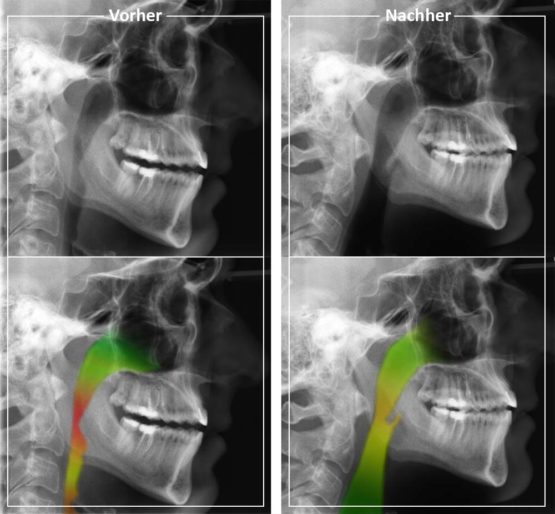

Schlafapnoe Operation Vorher Nachher. Schlafapnoe Welche Behandlungen gibt es Was können Sie selbst tun? Wie sich die Heilung der Schlafapnoe auch positiv auf das äußere Erscheinungsbild auswirkt +41 43 268 30 78 Kontaktformular Im Bereich „Nachher" konnten an der engsten Stelle 9,18 mm gemessen werden

Im unteren Bereich wurden die Atemwege zur Veranschaulichung eingefärbt Frau Madeleine Bovet, Schweiz "Täglich mehrfache Hustenreize, Müdigkeit, Erschöpfung und massive Schlafprobleme haben mich im 2014 veranlasst eine medizinische Abklärung vornehmen zu lassen.

Vor der OP hatte ich eher ein fliehendes Kinn, jetzt ist es etwas markanter Sie sehen auf den Vorher-Nachher-Fotos wie sich die Heilung der Schlafapnoe auch sehr positiv auf das. Auf dem Bild sind meine Röntgenbilder Vorher und Nachher